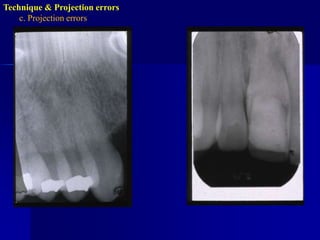

c. Projection errors:Incorrect vertical angulation.

Technique & Projection errorsc. Projection errorsIncorrect vertical angulationIt will lead to:Elongated image due to insufficient v. angulation ( too flat), or

Shortened image due to excessive v. angulation ( too steep)Technique & Projection errorsc. Projection errors

Technique & Projection errorsc. Projection errorsIncorrect horizontal angulationIs the appearance of the interproximal surfaces of the adjacent teeth over each other. This is due to improper H.A. due to improper alignment of the C.R. through the contact points i.e. not // to interproximal surfaces.

c. Projection errors:Incorrectvertical angulation.

Technique & Projectionerrorsc. Projection errorsIncorrect vertical angulationIt will lead to:Elongated image due to insufficient v. angulation ( too flat), or

Shortened image dueto excessive v. angulation ( too steep)Technique & Projection errorsc. Projection errors

Technique & Projectionerrorsc. Projection errorsIncorrect horizontal angulationIs the appearance of the interproximal surfaces of the adjacent teeth over each other. This is due to improper H.A. due to improper alignment of the C.R. through the contact points i.e. not // to interproximal surfaces.